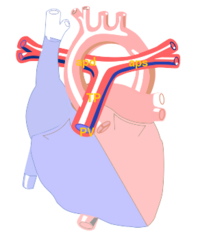

The pulmonary artery carries deoxygenated blood from the right ventricle to the lungs. It is the only artery that carries deoxygenated blood transported.

The pulmonary trunk (TP) starts from the pulmonary valve is ± 5 cm and ± 2 cm in diameter. Then splits into two branches, the trunk, the left-hand (aps) -, and right pulmonary artery (APD), which carry the oxygen-depleted blood to the corresponding lungs.